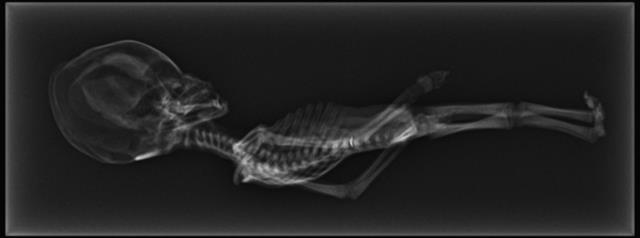

Ảnh chụp X-quang xác ướp Atacama. Ảnh: siriusdisclosure.com

Họ đã tiến hành xét nghiệm DNA, chụp X-quang và CT xác ướp, nhiều mẫu DNA chất lượng cao đã được trích xuất. Sau khi tiến hành phân tích, kết quả thu được rất kinh ngạc.